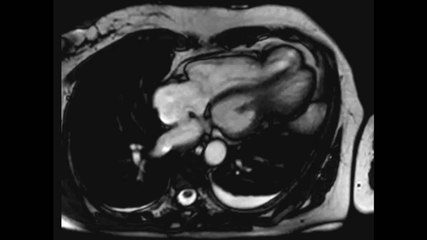

Video 2. Biventricular Broken Heart (Takotsubo Cardiomyopathy) in a Middle Aged Adult

Apical ballooning of the left and right ventricles are demonstrated.